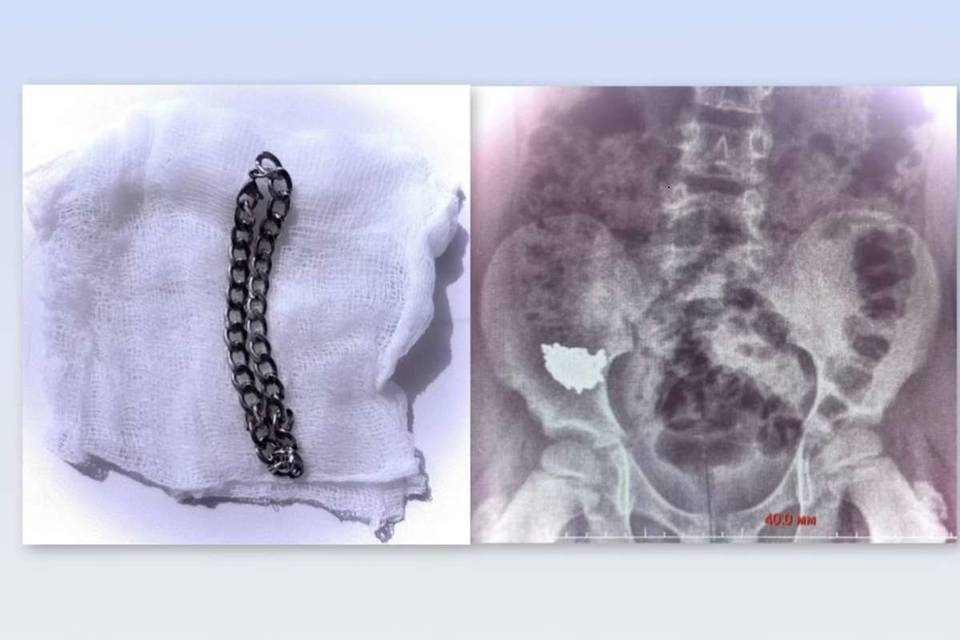

Сразу же после инцидента родители ребенка доставили его в больницу. Проведенный рентген показал, что украшение застряло внизу живота. Первые дни врачи наблюдали за школьников, проводя консервативное лечение. Однако снимки, сделанные на третьи и четвертые сутки, показали - инородное тело не двигается, оно словно застряло в кишечнике.

Так как имелся высокий риск образования отверстия в органе, было решено экстренно провести операцию Сначала юному пациенту под общим наркозом провели колоноскопию, но цепочку в толстой кишке не обнаружили. Затем хирурги провели ревизию в брюшной полости, обнаружили украшение и извлекли его через просвет аппендикса. Операцию завершили удалением червеобразного отростка.